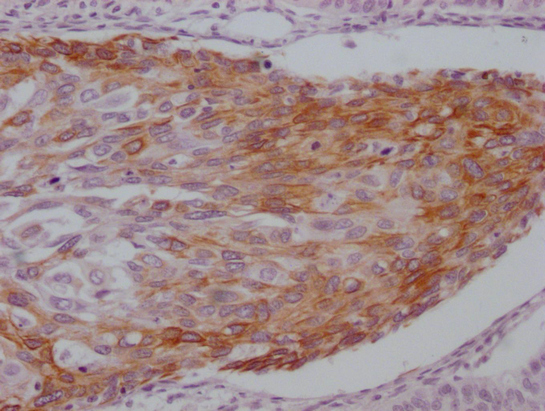

• IHC image of CSB-MA785224 diluted at 1:100 and staining in paraffin-embedded human breast cancer performed on a Leica BondTM system. After dewaxing and hydration, antigen retrieval was mediated by high pressure in a citrate buffer (pH 6.0). Section was blocked with 10% normal goat serum 30min at RT. Then primary antibody (1% BSA) was incubated at 4°C overnight. The primary is detected by a Goat anti-mouse IgG polymer labeled by HRP and visualized using 0.05% DAB.

• IHC image of CSB-MA785224 diluted at 1:100 and staining in paraffin-embedded human cervical cancer performed on a Leica BondTM system. After dewaxing and hydration, antigen retrieval was mediated by high pressure in a citrate buffer (pH 6.0). Section was blocked with 10% normal goat serum 30min at RT. Then primary antibody (1% BSA) was incubated at 4°C overnight. The primary is detected by a Goat anti-mouse IgG polymer labeled by HRP and visualized using 0.05% DAB.